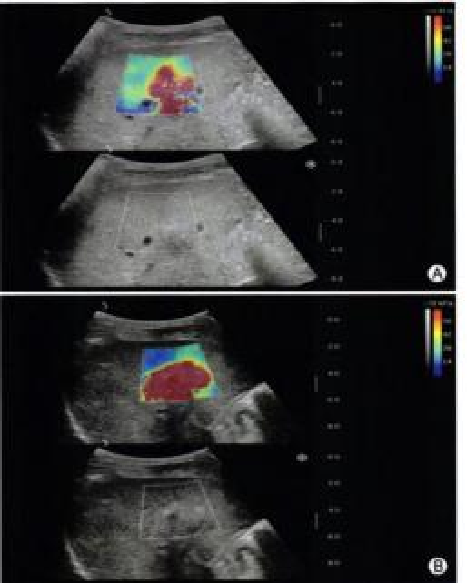

image.png

恶性占位常常向周边组织进行侵润及扩散,二维很难观察到浸润部分的边界。使用实时剪切波成像能够对占位及周边组织进行硬度评估,通过颜色编码来区分不同组织的硬度信息,直观的观察占位组织的边界信息,更方便区分占位组织和正常组织的边界,准确评估消融范围。

左图病例所示:

钼靶阴性,B型发现非肿块病变

剪切波弹性成像见明确的硬度增高区域。

穿刺及手术病理结果:浸润性导管癌(IDC)

非肿块型病变:B型图像无法确认病变范围,E成像帮助发现异常区域和评估